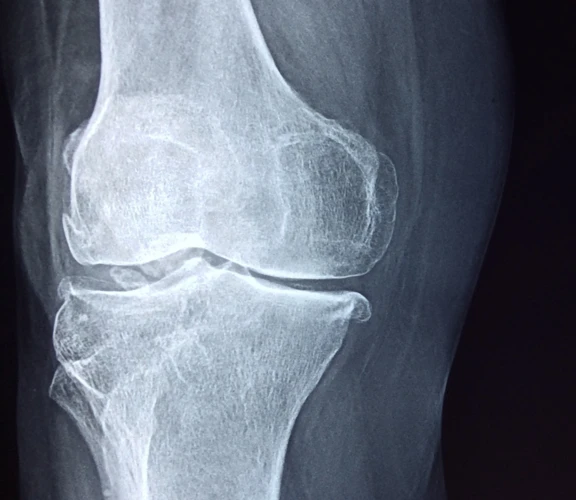

Osteoarthritis: a real story

Osteoarthritis is the most common type of arthritis, affecting 8.5 million people in the UK. It develops gradually over time, causing joints to become stiff and painful. It can affect any joint but commonly affects the hands, knees, hips, feet and spine.